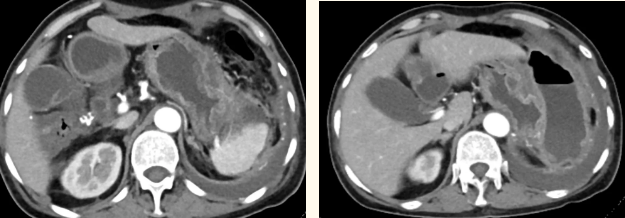

一籌莫展的她終于在病友的介紹下,來(lái)到西安國(guó)際醫(yī)學(xué)中心醫(yī)院找到蔡磊主任。經(jīng)過(guò)詢問病史,查體等,蔡磊主任建議口服索坦治療。3個(gè)月后,李阿姨復(fù)查CT提示胃間質(zhì)瘤較前明顯縮小,大小約10.4cm?6cm。但仍存在消化道出血,營(yíng)養(yǎng)狀況差,全身無(wú)力,骨髓抑制。蔡磊主任隨即將患者收治入院。